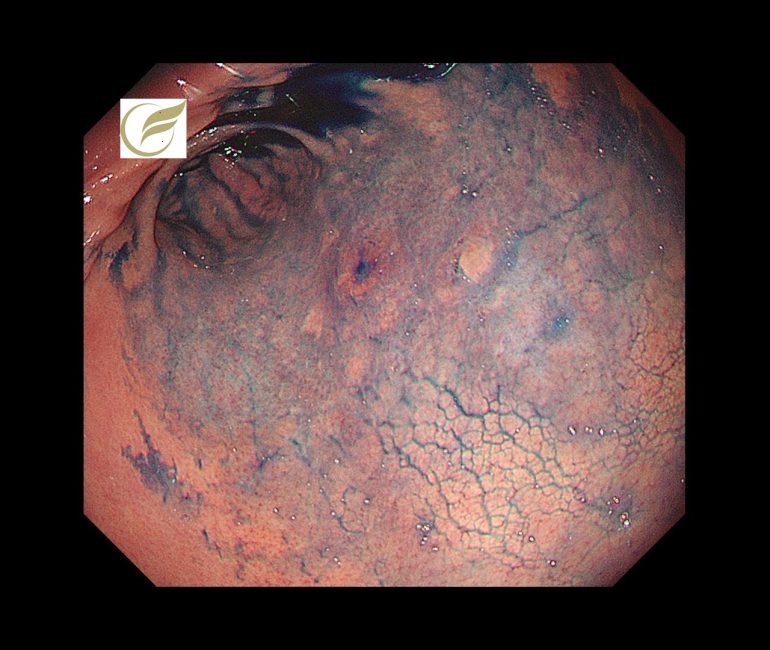

初期像は、内視鏡でわずかな退色調の平坦・陥凹病変として認められることが多く、早期診断には内視鏡観察が必要です(4)。

以下は当院で経験されたピロリ陰性の印環細胞癌(早期癌)の症例です。内視鏡治療で治癒が得られています。